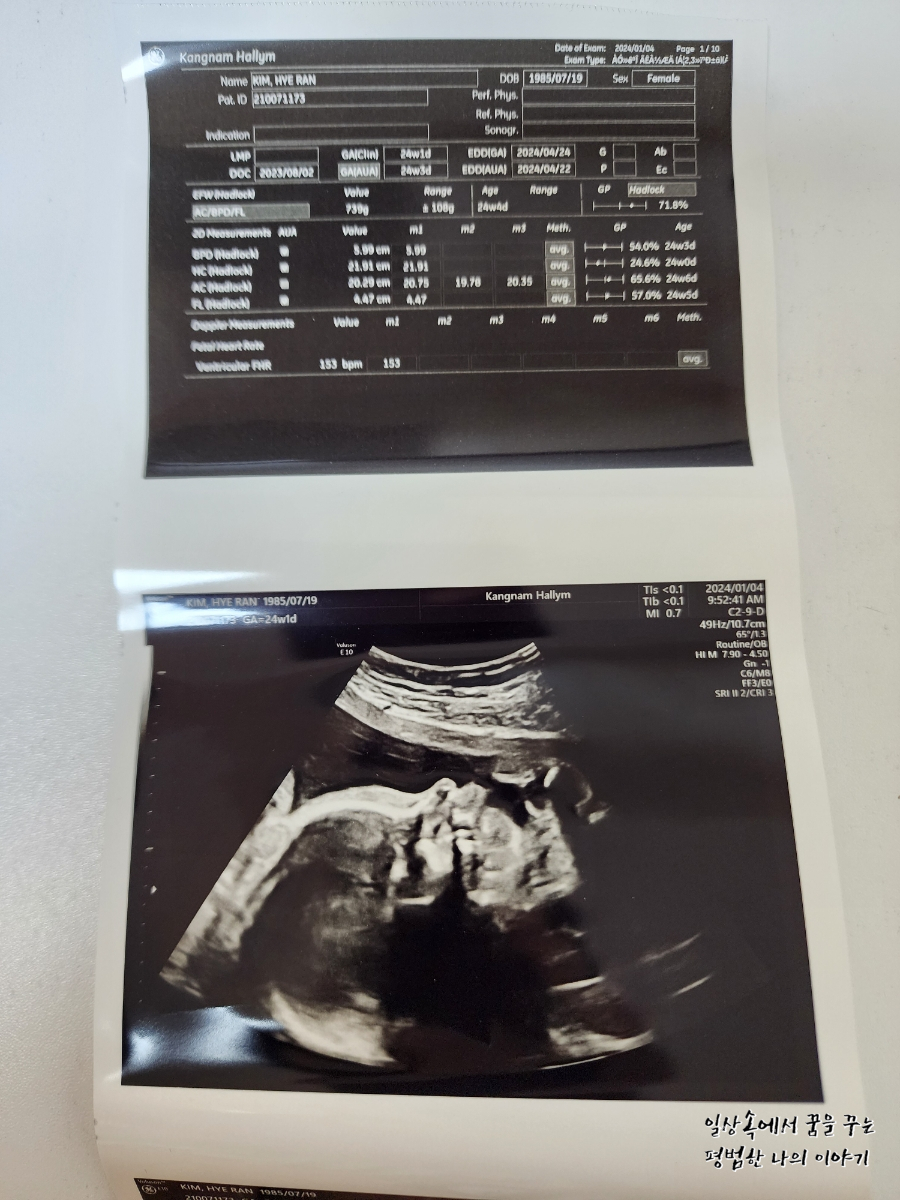

2024년 1월 4일(목요일)

BPD(Biparietal Diameter, 위에서 볼 때 태아 머리 단면의 가장 긴 길이): 5.99cm

HC(Head Circumference, 태아 머리둘레): 21.91cm

AC(Abdominal Circumference, 배 둘레): 20.29cm

EDD(Expected Date of Delivery, 출산 예정일): 2024년 4월 24일

FL(Femur Length, 허벅지뼈 길이): 4.47cm

GA(Gestational Age, 임신 주차): 24주 차 1일

EFW(Estimated Fatal Weight, 태아 예상 체중)=EBW(Estimated Body Weight): 757g

FHR(Fetal Heart Rate, 심장박동 수): 153bpm

CL(Cervical Length, 자궁경부 길이): 정상

AF(Amniotic Fluid, 양수): 정상